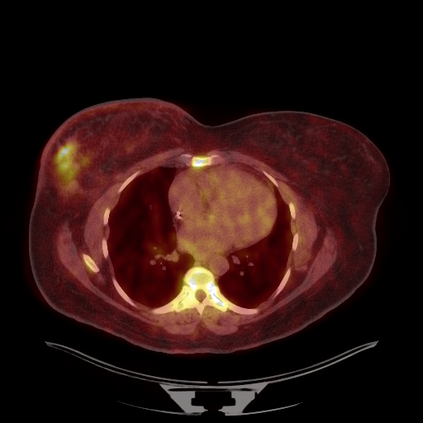

Medical images play a crucial role in assisting diagnosis, remote consultation, and academic research. However, during the transmission and sharing process, they face serious risks of copyright ownership and content tampering. Therefore, protecting medical images is of great importance. As an effective means of image copyright protection, zero-watermarking technology focuses on constructing watermarks without modifying the original carrier by extracting its stable features, which provides an ideal approach for protecting medical images. This paper aims to propose a fragile zero-watermarking model based on dual quaternion matrix decomposition, which utilizes the operational relationship between the standard part and the dual part of dual quaternions to correlate the original carrier image with the watermark image, and generates zero-watermarking information based on the characteristics of dual quaternion matrix decomposition, ultimately achieving copyright protection and content tampering detection for medical images.